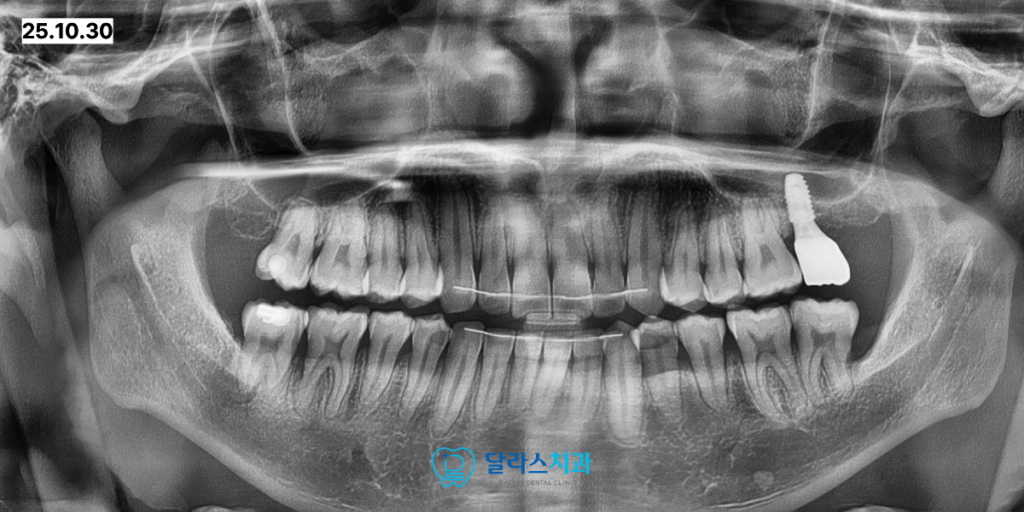

먼저 위쪽의 사랑니를 발치한 뒤 큰어금니를 끌어올릴 수 있도록 스크류를 식립하였습니다.

치료가 진행됨에 매복되어 있던 사십 칠 번 치아가 성공적으로 끌어올려진 모습을 볼 수 있습니다.

이 과정에서 앞쪽 큰어금니의 뿌리 뒷부분이 약간 흡수된 양상이 관찰되었습니다.

이는 매복치가 주변 치아에 미치는 나쁜 영향력을 보여주는 증거이기도 합니다.

인비절라인 교정을 통해 전체 치열을 가지런하게 정리한 뒤

임플란트 부위에 보철이 완성되었으며, 어금니가 바로세워졌습니다.